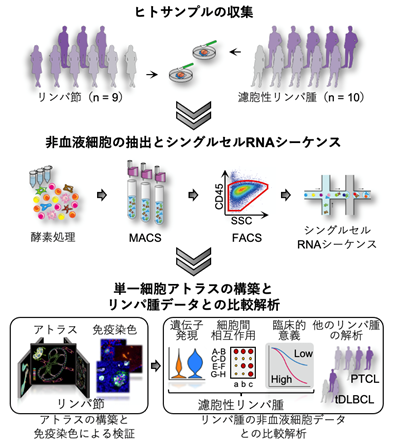

悪性リンパ腫の非血液細胞を分類・カタログ化した単一細胞アトラスを